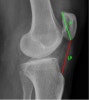

슬개고위증(Patella alta)와 슬개하위증(Patella baja)2016-10-09카테고리 106원본 보기 * 슬개고위증(Patella alta) : 선천적 변이나 슬개골 힘줄의 파열 * 슬개하위증(Patella baja) : 선천적 변이나 대퇴사두근건의 파열 ← 이전 글Knee Axial view에서의 Measurements다음 글 →Knee X-ray의 Anatomy와 Positioning같은 카테고리 글2017-06-10톰슨 검사(Thompson test) : 아킬레스건 파열을 조사하는 테스트2017-06-09Apley 압박 검사(Apley compression test) : 반월상 연골 손상을 조사하는 테스트2017-06-08맥머레이 시험(McMurray test) : 반월상 연골 손상을 조사하는 테스트← 전체 글로 돌아가기